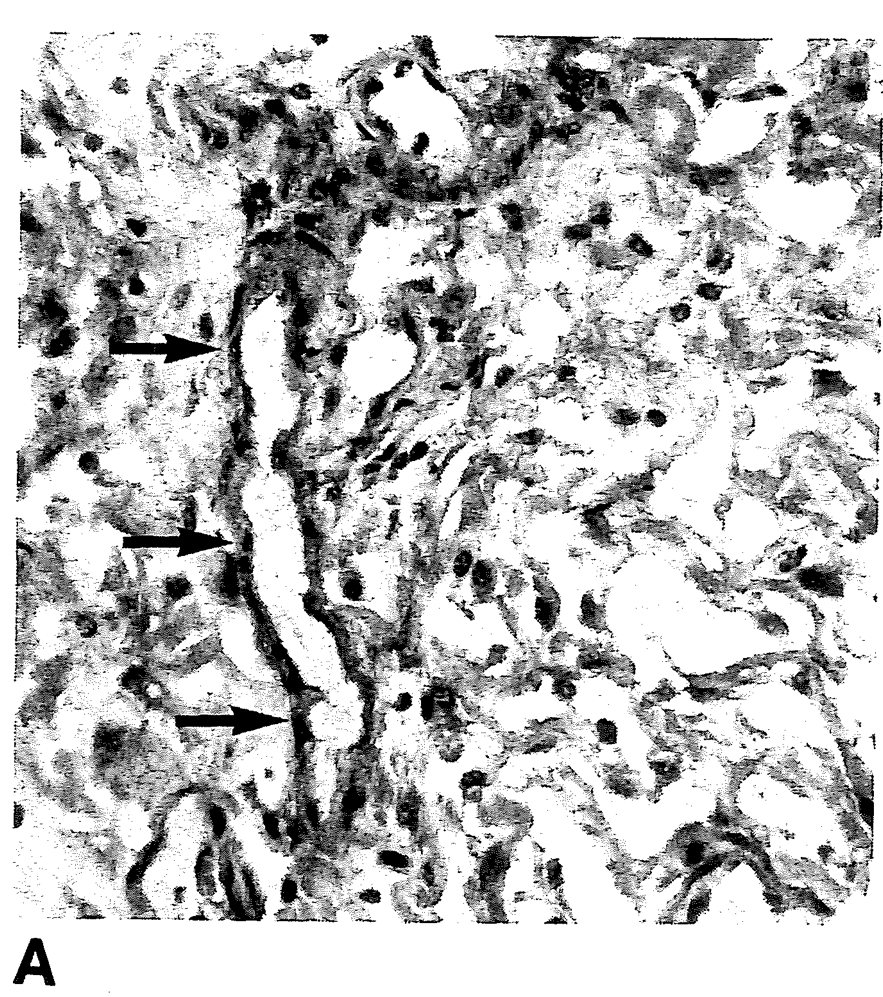

1991年Amis6)は、Amis論文の図2Aで後腹膜線維症の初期の炎症性段階の像を示し、図2Bで細胞性分の少ない後腹膜線維症の成熟期の病理像を説明しています。

図2A (Amis6)から引用 )

特異的プラーク形成の初期段階。細胞成分と血管造成(矢印)が認められ、浮腫的側面です。

図2A